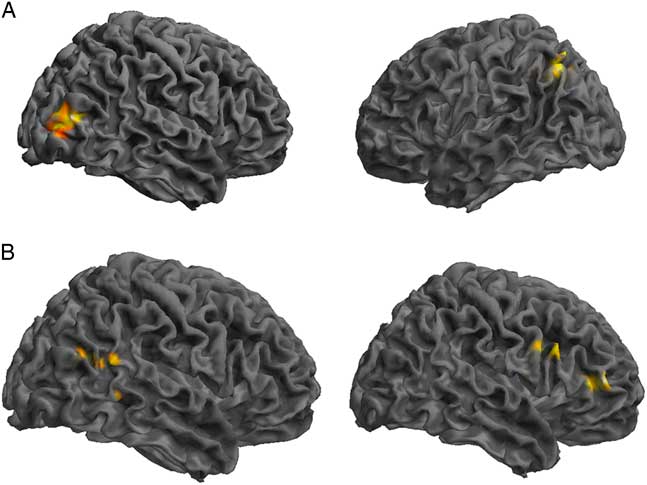

GICA Results: Control Group Compared to SRC Group

Comparing the DMN components between the control and SRC groups at time 1 revealed reduced functional connectivity in the SRC group compared to the control group (control>SRC) in the right inferior frontal gyrus (IFG), middle frontal gyrus (MFG), middle temporal gyrus (MTG), and posterior cingulate. Hyperconnectivity in the SRC group (SRC<control) was predominately seen in posterior regions, including left cerebellum and precuneus, and right middle occipital gyrus (MOG). No differences were found between the control and SRC groups at time 2 (Table 2; Figure 1).

Fig. 1 Significant differences in rs-fMRI functional connectivity between the SRC group and the control group at time 1. (A) Greater connectivity and (B) reduced connectivity in the SRC group compared to the control group. (A) Shown: right MOG and left precuneus; Not shown: left cerebellum. (B) Shown: right IFG, MFG, MTG, posterior cingulate.

Table 2 Differences at time 1 between the control group and the SRC group within the DMN component derived using GICA, in which greater functional connectivity in the SRC group is indicated by SRC>Control, and reduced functional connectivity in the SRC group is indicated by SRC<Control

L=left hemisphere; R=right hemisphere; BA=Brodmann area; MOG=middle occipital gyrus; IFG=inferior frontal gyrus; MFG=middle frontal gyrus; MTG=middle temporal gyrus.